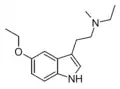

| 5-Ethoxy-DMT | artificial | 5-OCH2CH3 | CH3 | CH3 | 5-ethoxy-N,N-dimethyltryptamine | 855245-09-9 |

| 5-Ethoxy-MET | artificial | 5-OCH2CH3 | CH3 | CH2CH3 | 5-ethoxy-N-methyl-N-ethyltryptamine | |

| 5-Ethoxy-DET | artificial | 5-OCH2CH3 | CH2CH3 | CH2CH3 | 5-ethoxy-N,N-diethyltryptamine | |

| 5-Ethoxy-MPT | artificial | 5-OCH2CH3 | CH3 | CH2CH2CH3 | 5-ethoxy-N-methyl-N-propyltryptamine | |

| 5-Ethoxy-EPT | artificial | 5-OCH2CH3 | CH2CH3 | CH2CH2CH3 | 5-ethoxy-N-ethyl-N-propyltryptamine | |

| 5-Ethoxy-DPT | artificial | 5-OCH2CH3 | CH2CH2CH3 | CH2CH3 | 5-ethoxy-N,N-dipropyltryptamine | |

| 5-Ethoxy-MiPT | artificial | 5-OCH2CH3 | CH3 | CH(CH3)2 | 5-ethoxy-N-methyl-N-isopropyltryptamine | |

| 5-Ethoxy-EiPT | artificial | 5-OCH2CH3 | CH2CH3 | CH(CH3)2 | 5-ethoxy-N-ethyl-N-isopropyltryptamine | |

| 5-Ethoxy-DiPT | artificial | 5-OCH2CH3 | CH(CH3)2 | CH(CH3)2 | 5-ethoxy-N,N-diisopropyltryptamine | |

| 5-Ethoxy-DALT | artificial | 5-OCH2CH3 | H2C=CH-CH2 | H2C=CH-CH2 | 5-ethoxy-N,N-diallyltryptamine | |